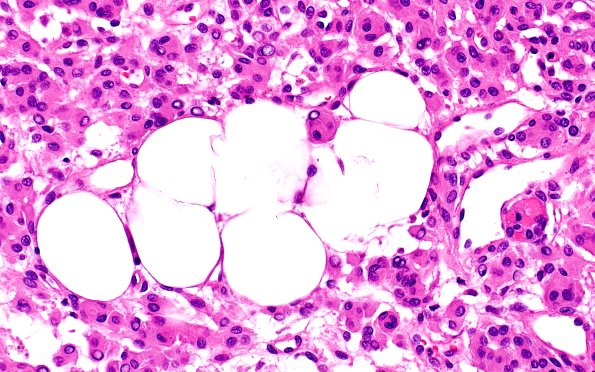

17C5 Meningioma, lipidized (Case 17) 40X 2

17C5,6 Higher magnification images show fat within tumor cells. (H&E)